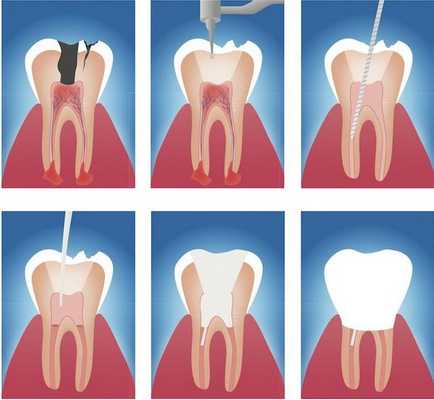

Данный метод лечения нацелен на устранение патогенной микрофлоры, находящейся в эндодонте — комплексе поражённых тканей, включающем пульпу и дентин, которые связаны между собой морфологически и функционально. Поэтому иначе такое лечение называют эндодонтическим. [16]

Этапы эндодонтического лечения:

- адекватное обезболивание;

- изоляция зуба или нескольких зубов, в которых будут проводится манипуляции, от полости рта;

- создание эндодонтического доступа (иссечение твёрдых тканей зуба или пломбировочного материала, закрывающих доступ в систему корневого канала;

- прохождение и определение длинны корневого канала (это длинна от устья до верхушки корня);

- создание корневого канала определённого диаметра и формы;

- введение в корневой канал лекарственных препаратов;

- пломбирование корневого канала;

- восстановление анатомии и функции зуба с помощью пломбировочного материала или ортопедической конструкции.